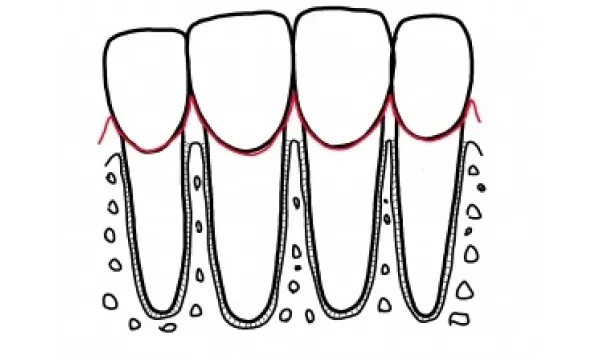

歯周病は、歯の周りの組織の病気です。 歯周病の原因である細菌に侵されると炎症は、 歯肉→歯と歯肉をつなぐ組織→歯と骨をつなぐ組織→骨というように進行していきます。 右に向かうほど炎症が強いといえます。

歯周病の初期の段階は歯肉炎と言います。歯肉炎では、歯周病菌が歯と歯肉の間に入り込み、プラークや歯石がたまりはじめます。 歯肉炎が進むと、歯と歯肉の間に歯周ポケットができて歯周ポケットにプラークや歯石がたまってきます。この状態を放置すると、歯周ポケットが深くなり、歯肉が腫れたり、出血するようになります。 そして、さらに歯周病が進行すると、歯槽骨が溶けはじめ、歯が支えられなくなります。最終的には歯が抜けてしまうことになります。皆様の大切な歯を守るためには、初期の段階から治療や正しいケアが必要です。

歯周病治療を行った結果、炎症がコントロールされた状態とは、炎症がなくなり(歯肉からの出血がなくなり)、最近との共生関係が確立(細菌がいなくなるのではなく影響がなくなる)その環境が永続しやすいような状態(浅いポケット)になることです。 残念ながらそれは、以前のように歯の間が歯肉に満たされ、骨が上まである状態ではありません。吸収してしまった骨は基本的には元には戻らず、歯肉は下がった状態で安定します。図に書くと以下のようになります。

これは正常な歯周組織

根の間に上まで歯槽骨があり、歯の間は歯肉で覆われています。